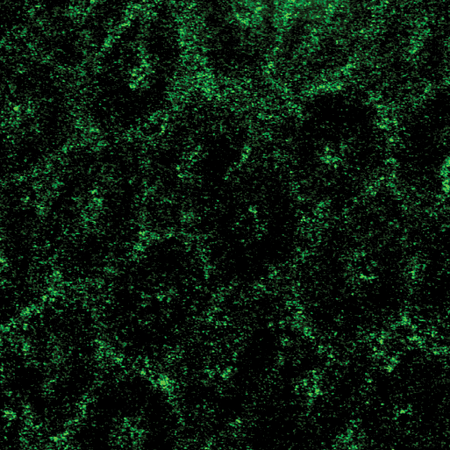

Performing their experiments in mice, the team tested the effects of polymers, which include dietary fiber as well as therapeutics such as medicines for constipation. The researchers fed some mice a diet rich in polymers and others (the controls) a polymer-free diet. Using a technique called confocal reflectance microscopy they measured the thickness of the gut gel and the degree to which the gel was compressed as a result of the consumed polymers. Mice given a high-polymer diet, they found, had a more compressed gel layer.

"The gel is like a sponge with holes that let material through," says the paper's lead author, Sujit Datta, a postdoctoral scholar in the laboratory of Rustem Ismagilov, Ethel Wilson Bowles and Robert Bowles Professor of Chemistry and Chemical Engineering. "We are seeing that polymers, including dietary fiber, can compress the gel, potentially making the holes smaller, and we think that this might offer protective benefits," Datta adds.

The researchers also found that dietary fiber and gut bacteria—which are part of a community of microorganisms collectively known as gut microbiota—can work together to influence how the gut gel changes shape. They performed the same polymer/fiber experiments in germ-free mice, which are mice carefully raised to not have any bacteria in their gut. The results showed that the polymers compressed the gut gels of these germ-free mice to a greater degree. This implies that species of bacteria in our gut that are known to break down polymers can weaken the compressing effect.